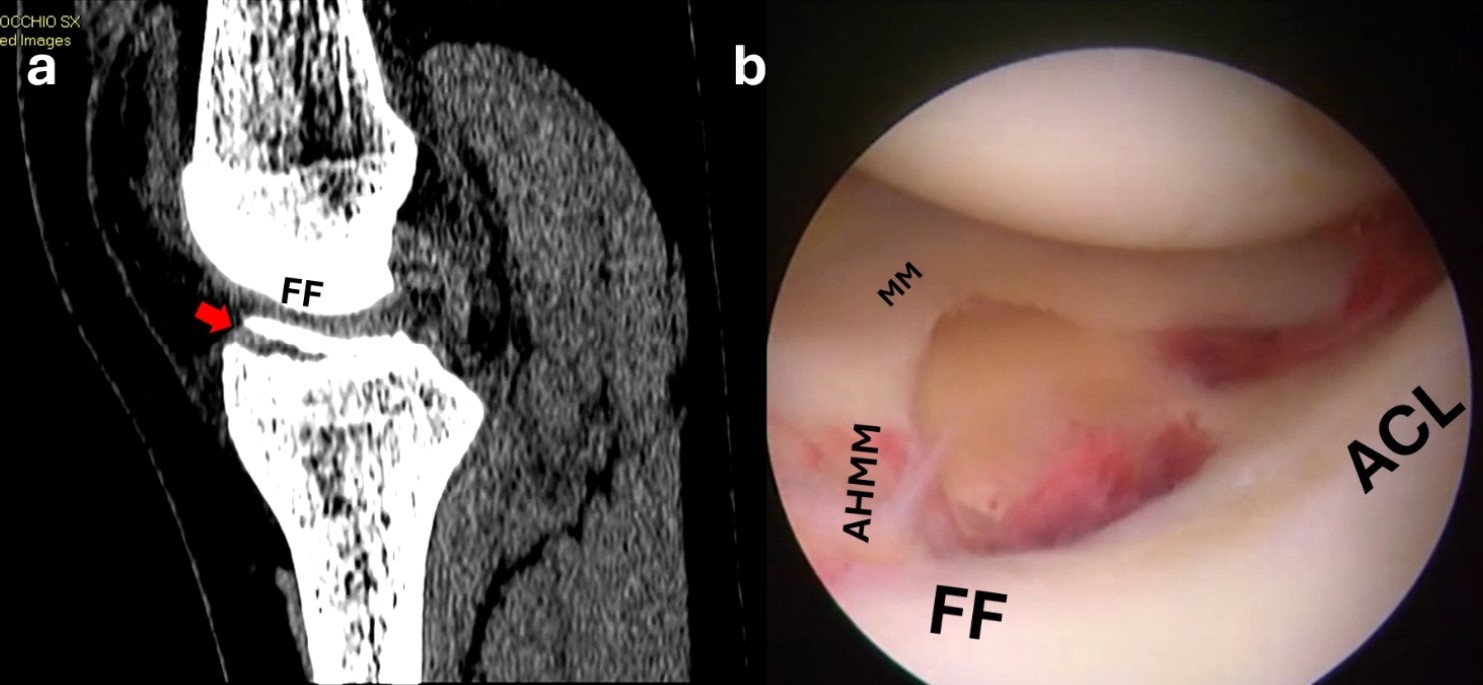

Figure 1. Sagittal CT scan showing a displaced anterior eminence fracture (red arrow) (a); the arthroscopic view shows the interposition of the intermeniscal ligament and the fracture bed (b). FF, fracture fragment; MM, medial meniscus; MFC, medial femoral condyle.

Figure 6. Sagittal CT scan showing a displaced anterior eminence fracture (red arrow) (a); the arthroscopic view shows the interposition of the anterior horn of the medial meniscus and the fracture bed (b).

FF, fracture fragment; MM, medial meniscus; AHMM, anterior horn of the medial meniscus; ACL, anterior cruciate ligament.